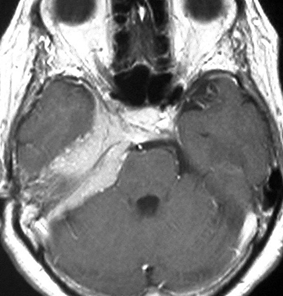

左は,造影剤を使ったガドリニウム増強MRIです。腫瘍が白く丸く見えます。右はフレア画像で,腫瘍の周囲の脳浮腫(脳のはれ)です。左前頭葉が,かなり強くはれています。この腫瘍は小さいのですが,脳のはれが強すぎるので手術摘出したほうがいいです。浮腫が悪化すると,てんかん発作や認知機能低下がでる可能性があります。